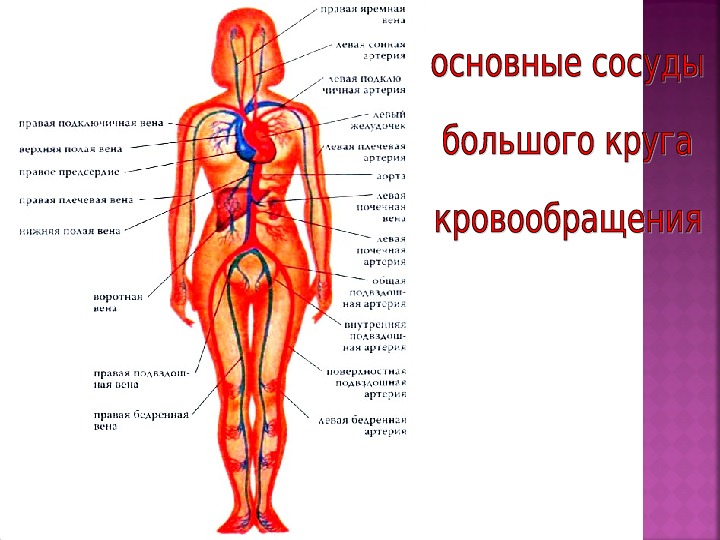

Анатомия человека: кровеносная система и её связь со скелетом